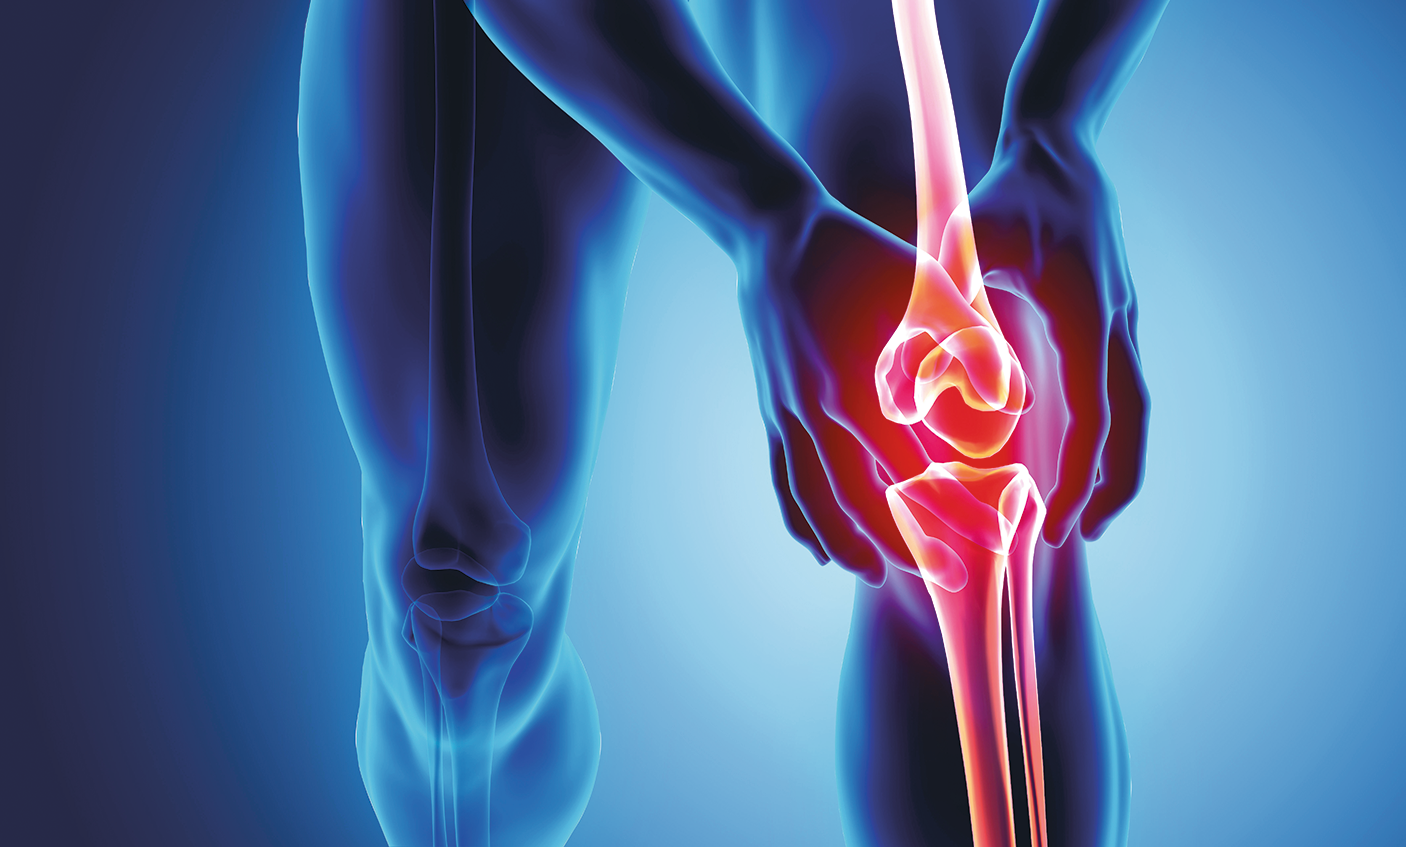

Раздел: Фотозарисовки